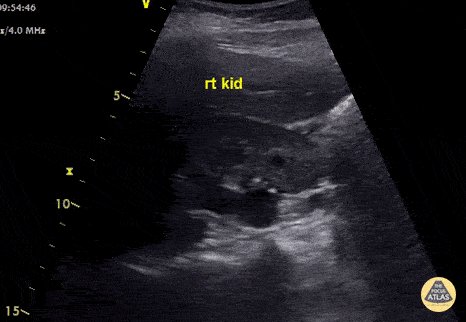

14 - Moderate hydronephrosis